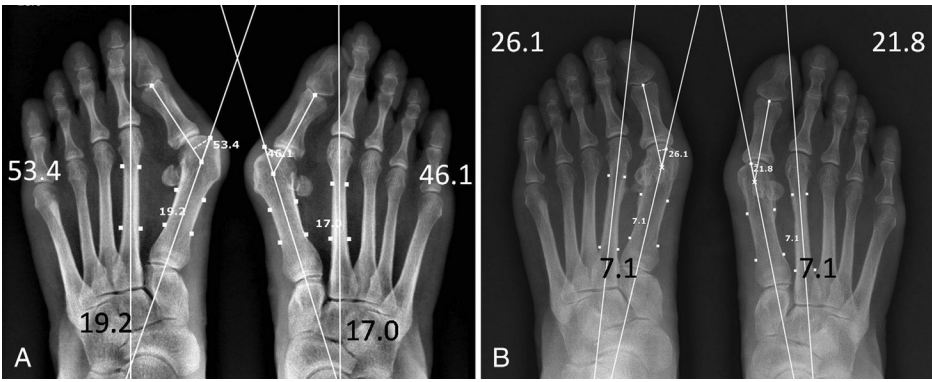

▲图示(A)47 岁女性中重度拇外翻畸形的影像学片,该患者双足均存在跖趾关节不匹配及跖籽韧带完全分离。(B)术后 2 年随访影像学片。第一跖骨复位效果良好;未松解拇收肌腱,仅分别对跖趾关节韧带、跖籽韧带进行松解,拇趾与籽骨也均实现良好复位。

▲图示(A)59 岁女性重度拇外翻的影像学片,该患者自青少年时期起即患有双侧拇外翻畸形,且因工作原因穿高跟鞋的年限超 20 年,其主要症状为跖骨痛。(B)术后 3 年随访的影像学片。尽管第一跖骨与籽骨的对位关系维持良好,但患足仍残留中度拇外翻畸形;不过该患者恢复了跑步能力,且可再次穿高跟鞋,同时跖部胼胝消失、跖骨痛症状缓解,对此效果表示满意。

▲图示(A)75 岁女性患者术前站立位 X 线片示:双足畸形严重;双足美国足踝外科协会(AOFAS)拇趾评分均为 60 分;双足足趾跖趾关节角分别为 45.4° 和 50.8°,跖骨间角分别为 17.1° 和 20.1°。(B)术后 2 年站立位 X 线片示:第一跖骨内翻矫正效果满意,但因拇短屈肌外侧头可能存在挛缩,残留轻度拇外翻畸形;患者远端跖骨关节角轻度增大;右足 AOFAS 拇趾评分为 83 分,左足为 93 分。

▲图示(A)54 岁女性患者术前站立位 X 线片示:双足存在典型且无合并症的第一序列三联畸形,即拇外翻、第一跖骨内翻及跖籽分离,畸形程度为中度;术前美国足踝外科协会(AOFAS)拇趾评分为双足均 70 分。(B)术后 3 年站立位 X 线片示:拇趾、第一跖骨及籽骨复位满意,双足 AOFAS 拇趾评分均达 100 分。